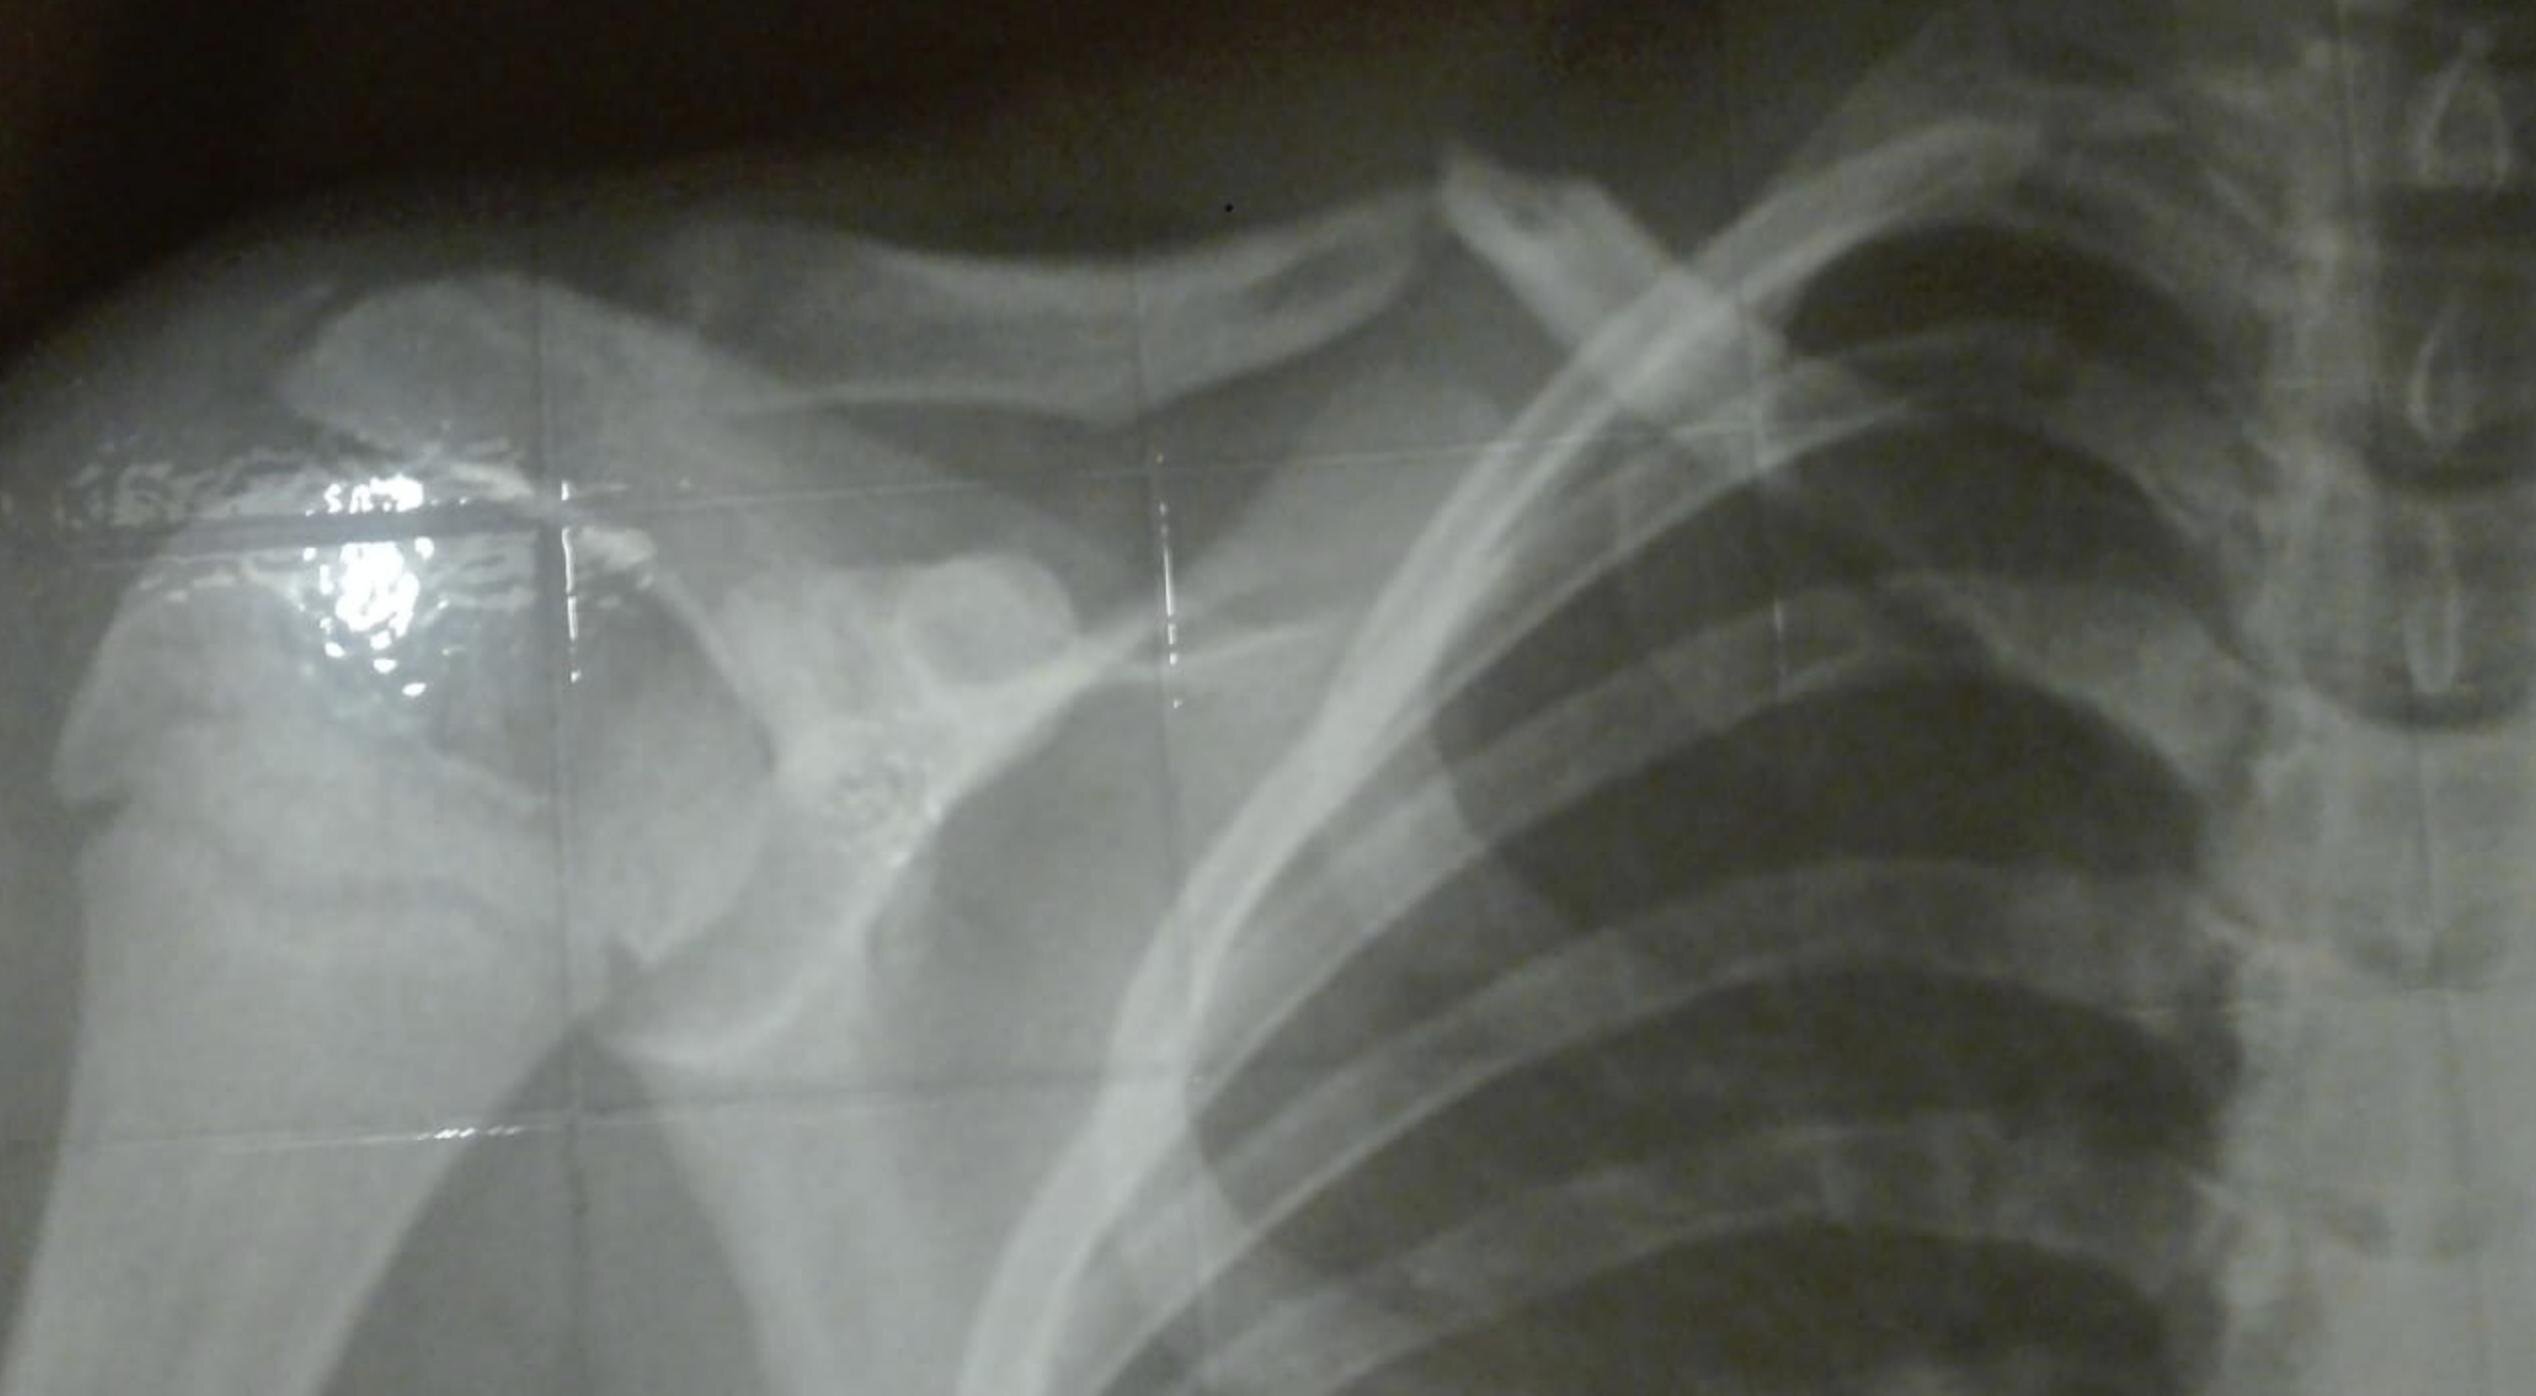

Uno de los ejemplos de operación publicados por Peláez en su cuenta de Twitter: